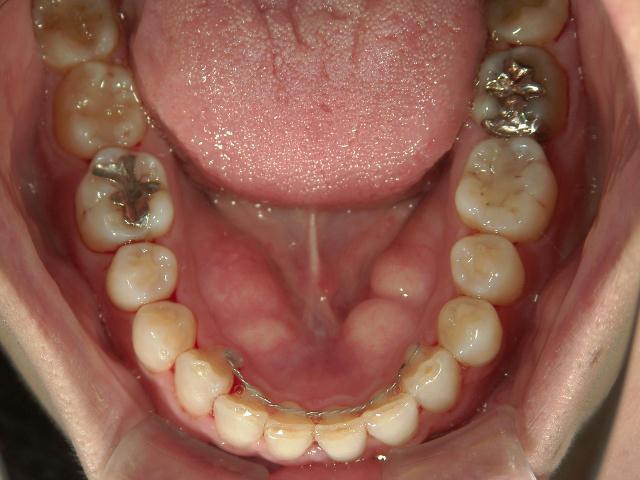

矯正歯科 治療前

36歳女性 磐田市

在住

治療期間2年6

ヶ月